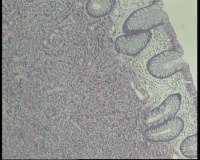

息肉三个为腺瘤,这里就不拍图了,其中一个稍小的0.6x0.6x0.4厘米的,切面发黄,质硬,表面光滑,镜下瘤细胞圆形、卵圆形、柱状,呈腺样、索条状排列,无明显核分裂,神经内分泌肿瘤GI吗?(图1,2为表面,最后一图为切缘,切缘一个很窄的小边为纤维脂肪组织没有瘤细胞,这能算切缘净吗?还是报瘤组织紧贴切缘?)

神经内分泌肿瘤G1

神经内分泌肿瘤,G1,切缘干净但少于1毫米,随访。

神经内分泌肿瘤,关于分级,核分裂找不到的话参考一下Ki67,肿瘤与切缘间的距离用测微尺测一下。